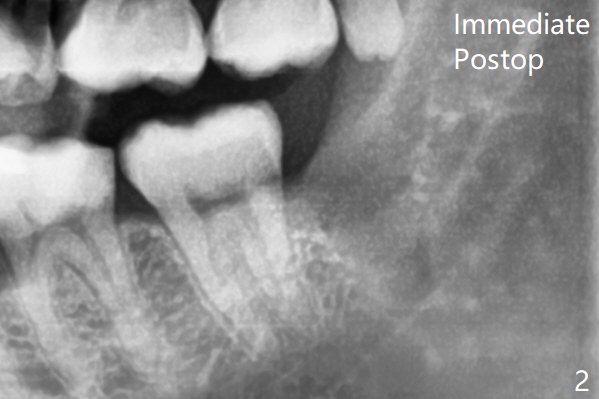

The tooth is out following sectioning twice with the socket inserted with Osteogen plug (Fig.2).